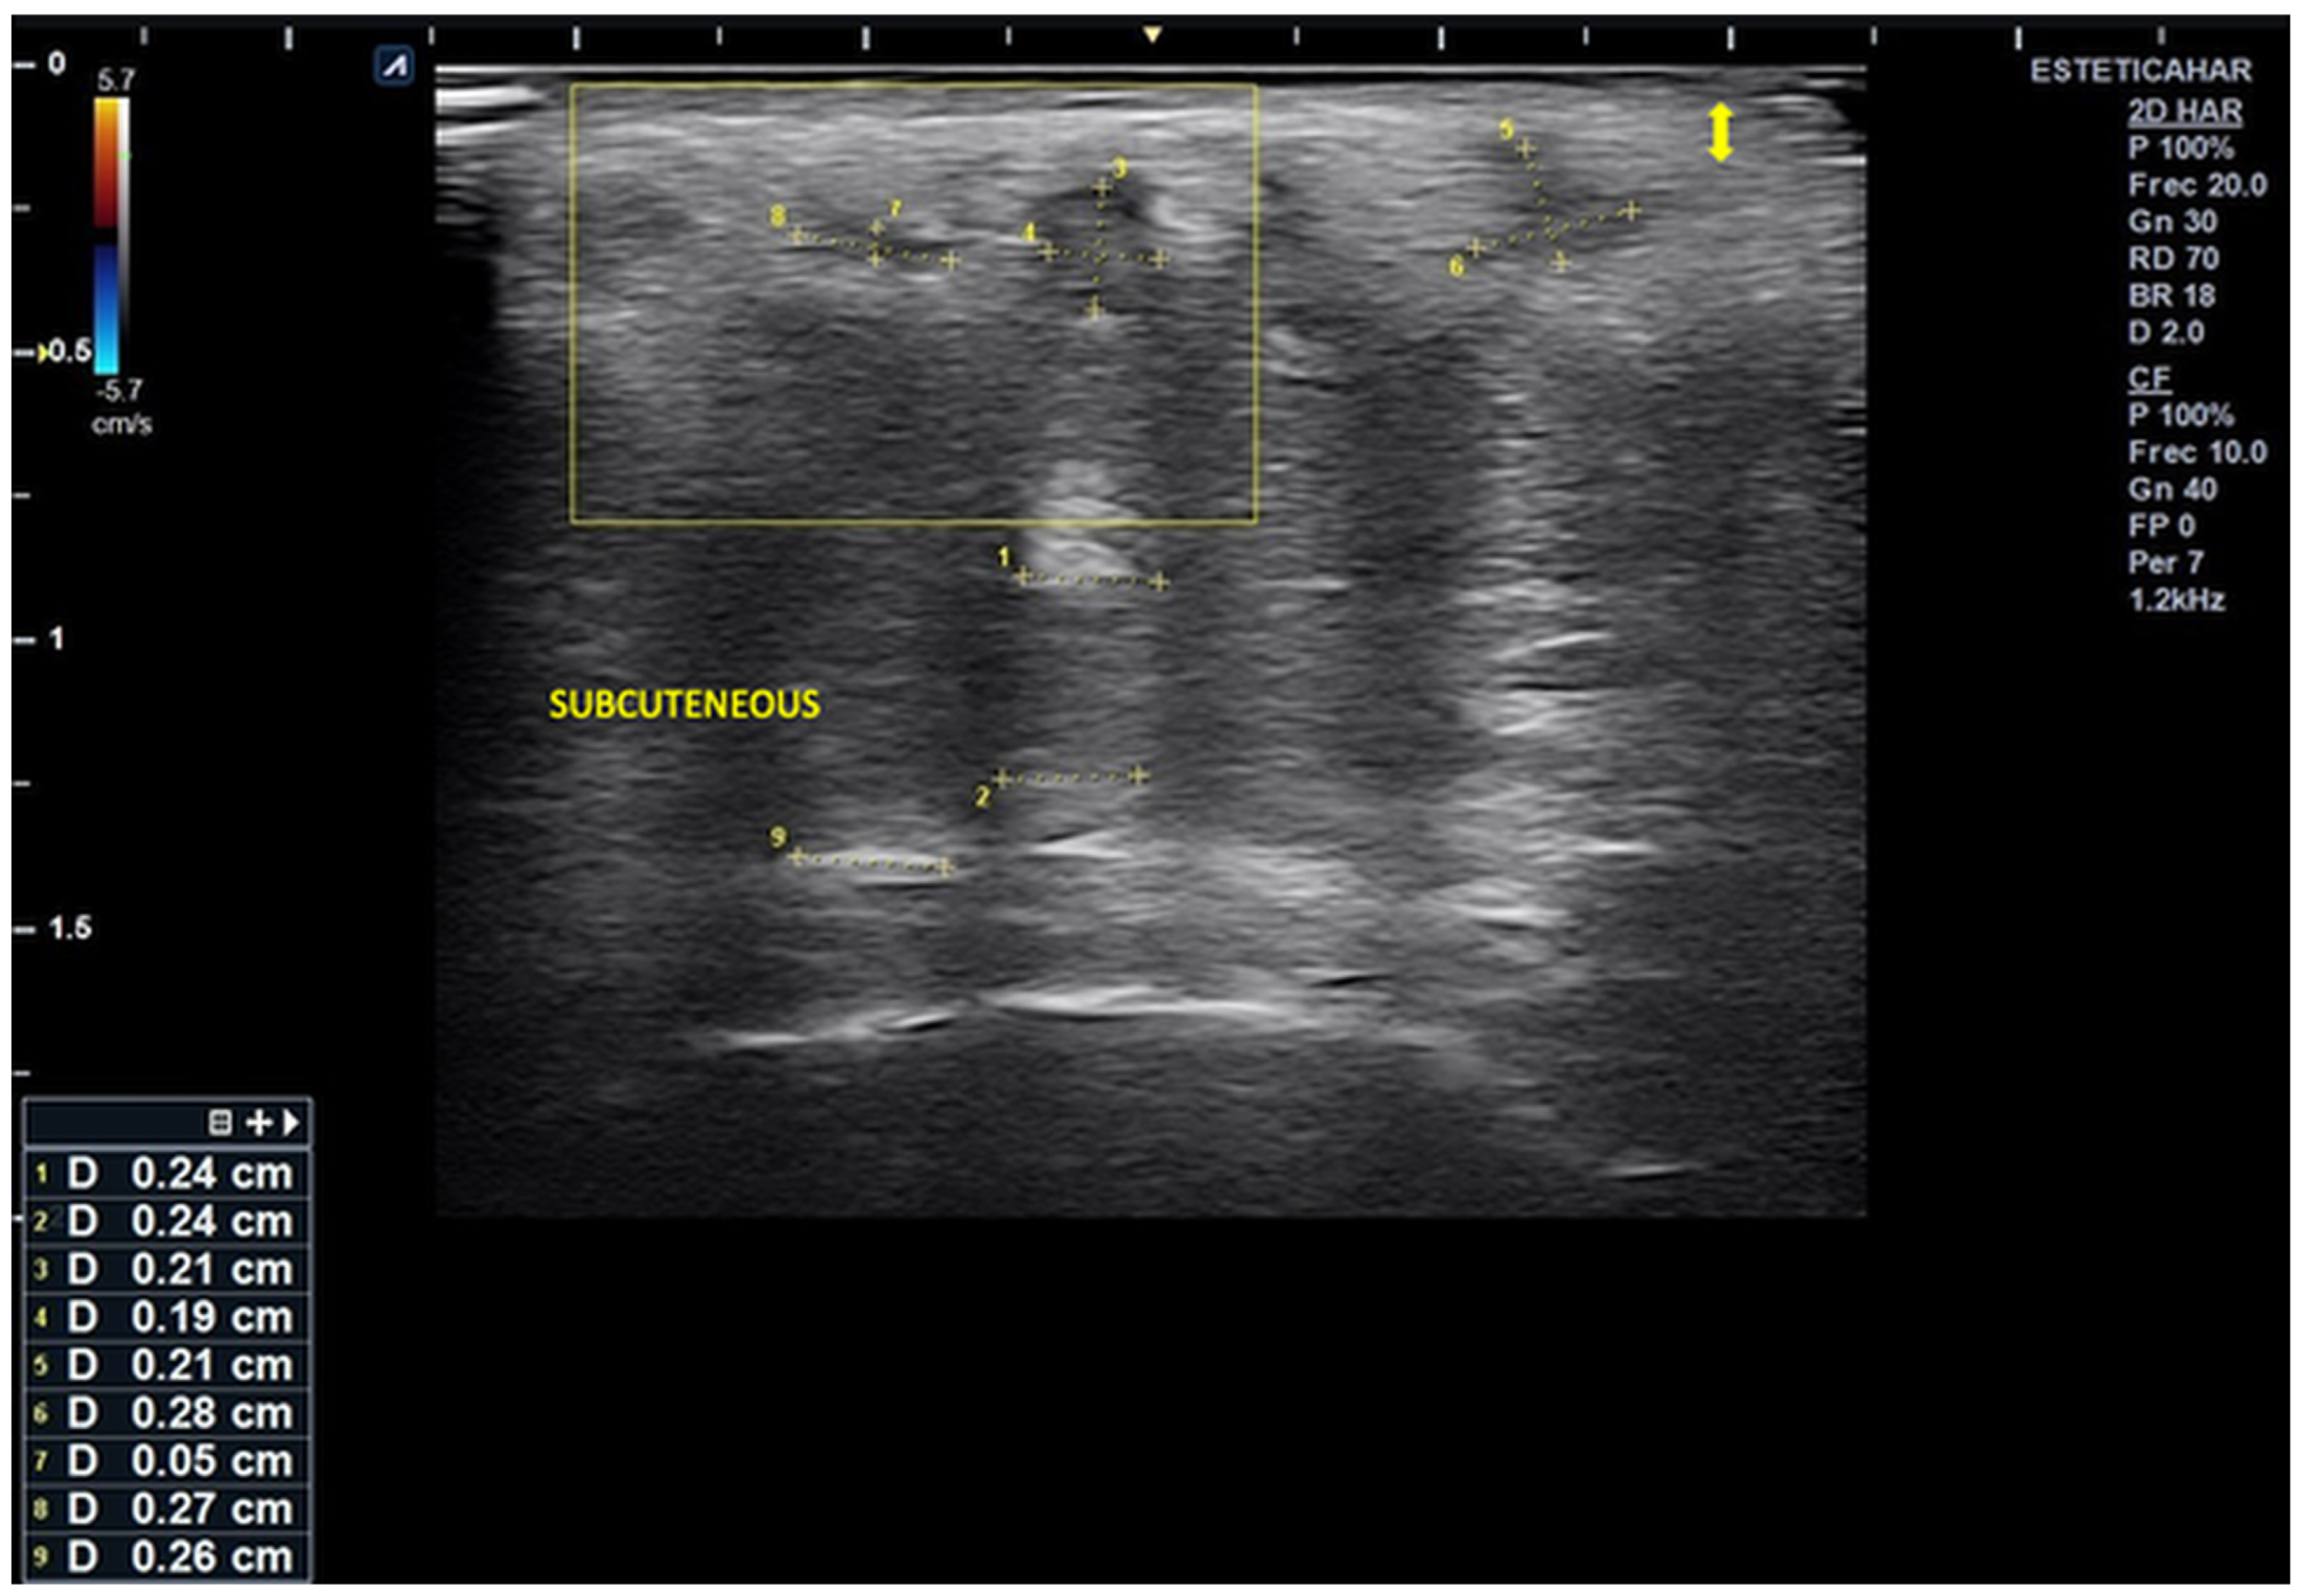

). The scan reveals alternating hyper- and hypoechoic columnar areas extending from the posterior dermis to the bone plane, which hinder clear differentiation of tissue layers based on echogenicity. The largest area, measuring 0.24 cm in width, is most likely associated with deposits of hybrid material (hyperdiluted collagen stimulator). Additionally, three smaller, rounded hypoechoic deposits are observed in the more superficial subcutaneous region. The largest of these measures 0.27 × 0.26 cm and is likely associated with poor integration of the injected material, without evidence of increased microvascularization.